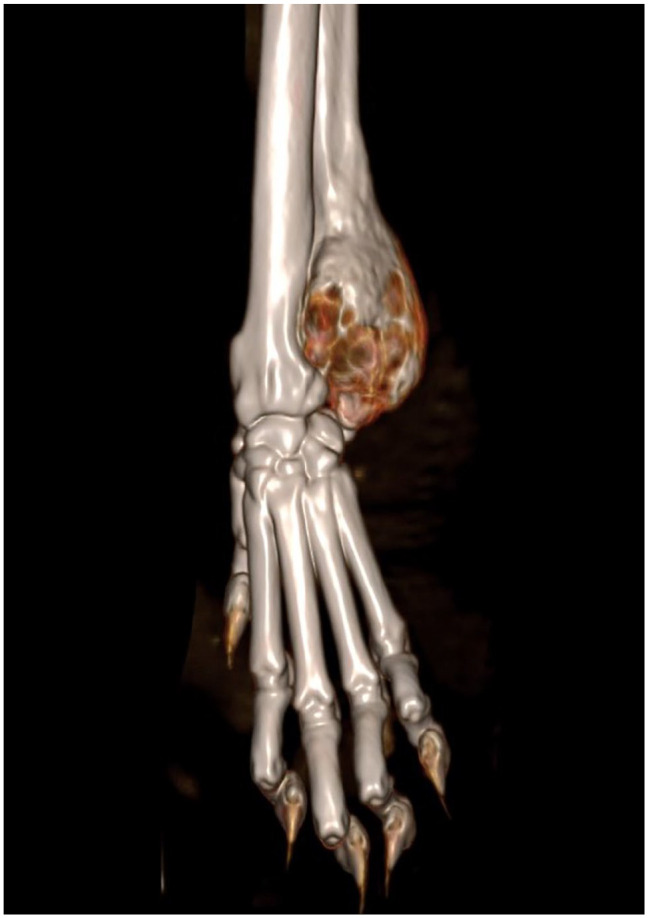

Case summary: An 8-year-old male neutered domestic shorthair cat was presented with an acute onset of left thoracic limb lameness and a firm swelling on the lateral aspect of the left distal antebrachium. A CT scan of the left thoracic limb revealed an expansile osteolytic cystic bone lesion centred at the distal left ulnar metaphysis. Cytology from fine-needle aspiration was not consistent with neoplasia. The CT features and the cytology results were suggestive of a bone cyst. A distal partial ulnectomy with ulnar styloid process excision was performed as the biopsy method and as the treatment approach. Histopathology results were consistent with an aneurysmal bone cyst (ABC). Carpal instability was not detected after distal partial ulnectomy; therefore, a stabilisation method was not required. Limb function was excellent after surgery, with no lameness and no recurrence detected by the owner at 2, 6 and 24 weeks postoperatively. The veterinary examination at 12 weeks postoperatively confirmed the owner's outcome assessment.

Relevance and novel information: To the authors' knowledge, this is the first report describing a distal partial ulnectomy with ulnar styloid process excision in a cat. Despite disrupting the short ulnar collateral ligament, this technique provided excellent short-term limb function with no need for carpal joint stabilisation. This technique allowed for the complete excision of a distal ulnar ABC and avoided cyst debridement, which could be associated with haemorrhage, recurrence and malignant transformation. Distal partial ulnectomy should be considered for distal ulnar bone lesions in cats.